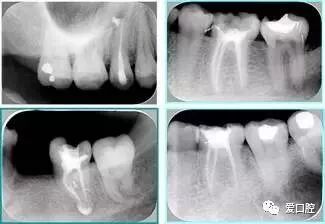

( 2 )X片共四张 (术前、诊断丝 、主牙胶尖确认、术后)。

共有 4 张 X 线片,分别是术前、诊断丝 、主牙胶尖确认、术后。

( 1 )术前:术前 X 线片用来了解牙齿的大概情况。术前预期为多根牙时 X 线片应偏头拍摄。

( 2 )诊断丝:根据术前 X 线片进行开髓、根管的初步预备后,需要插入诊断丝,用来指示工作器械位置。常用 10 号或 15 号扩大器作为诊断丝插入牙髓腔。

( 3 )主牙胶尖确认:通过术前预期和诊断丝诊断,明确工作长度、牙根走向,进行根管预备。之后应进行主牙胶尖(中锉)确认,已明确根管是否适合充填。

( 4 )术后:观察治疗效果。